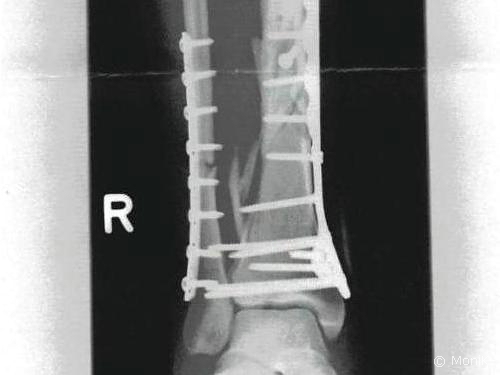

Ergebnis: Offene multiple Unterschenkelfraktur. Aha. Gespräch mit dem Oberarzt, der mich operieren wird. Blick auf die Röntgenbilder, aus denen ich die Schwere der Verletzung dennoch nicht richtig registriere. Ok, das Wadenbein ist einmal, das Schienbein mehrfach gebrochen, das Sprunggelenk hat auch einen Riss. Platten und Schrauben sollen es richten. Na, dann macht mal. Kann doch nicht so wild sein, war doch nur ein Umfaller!?